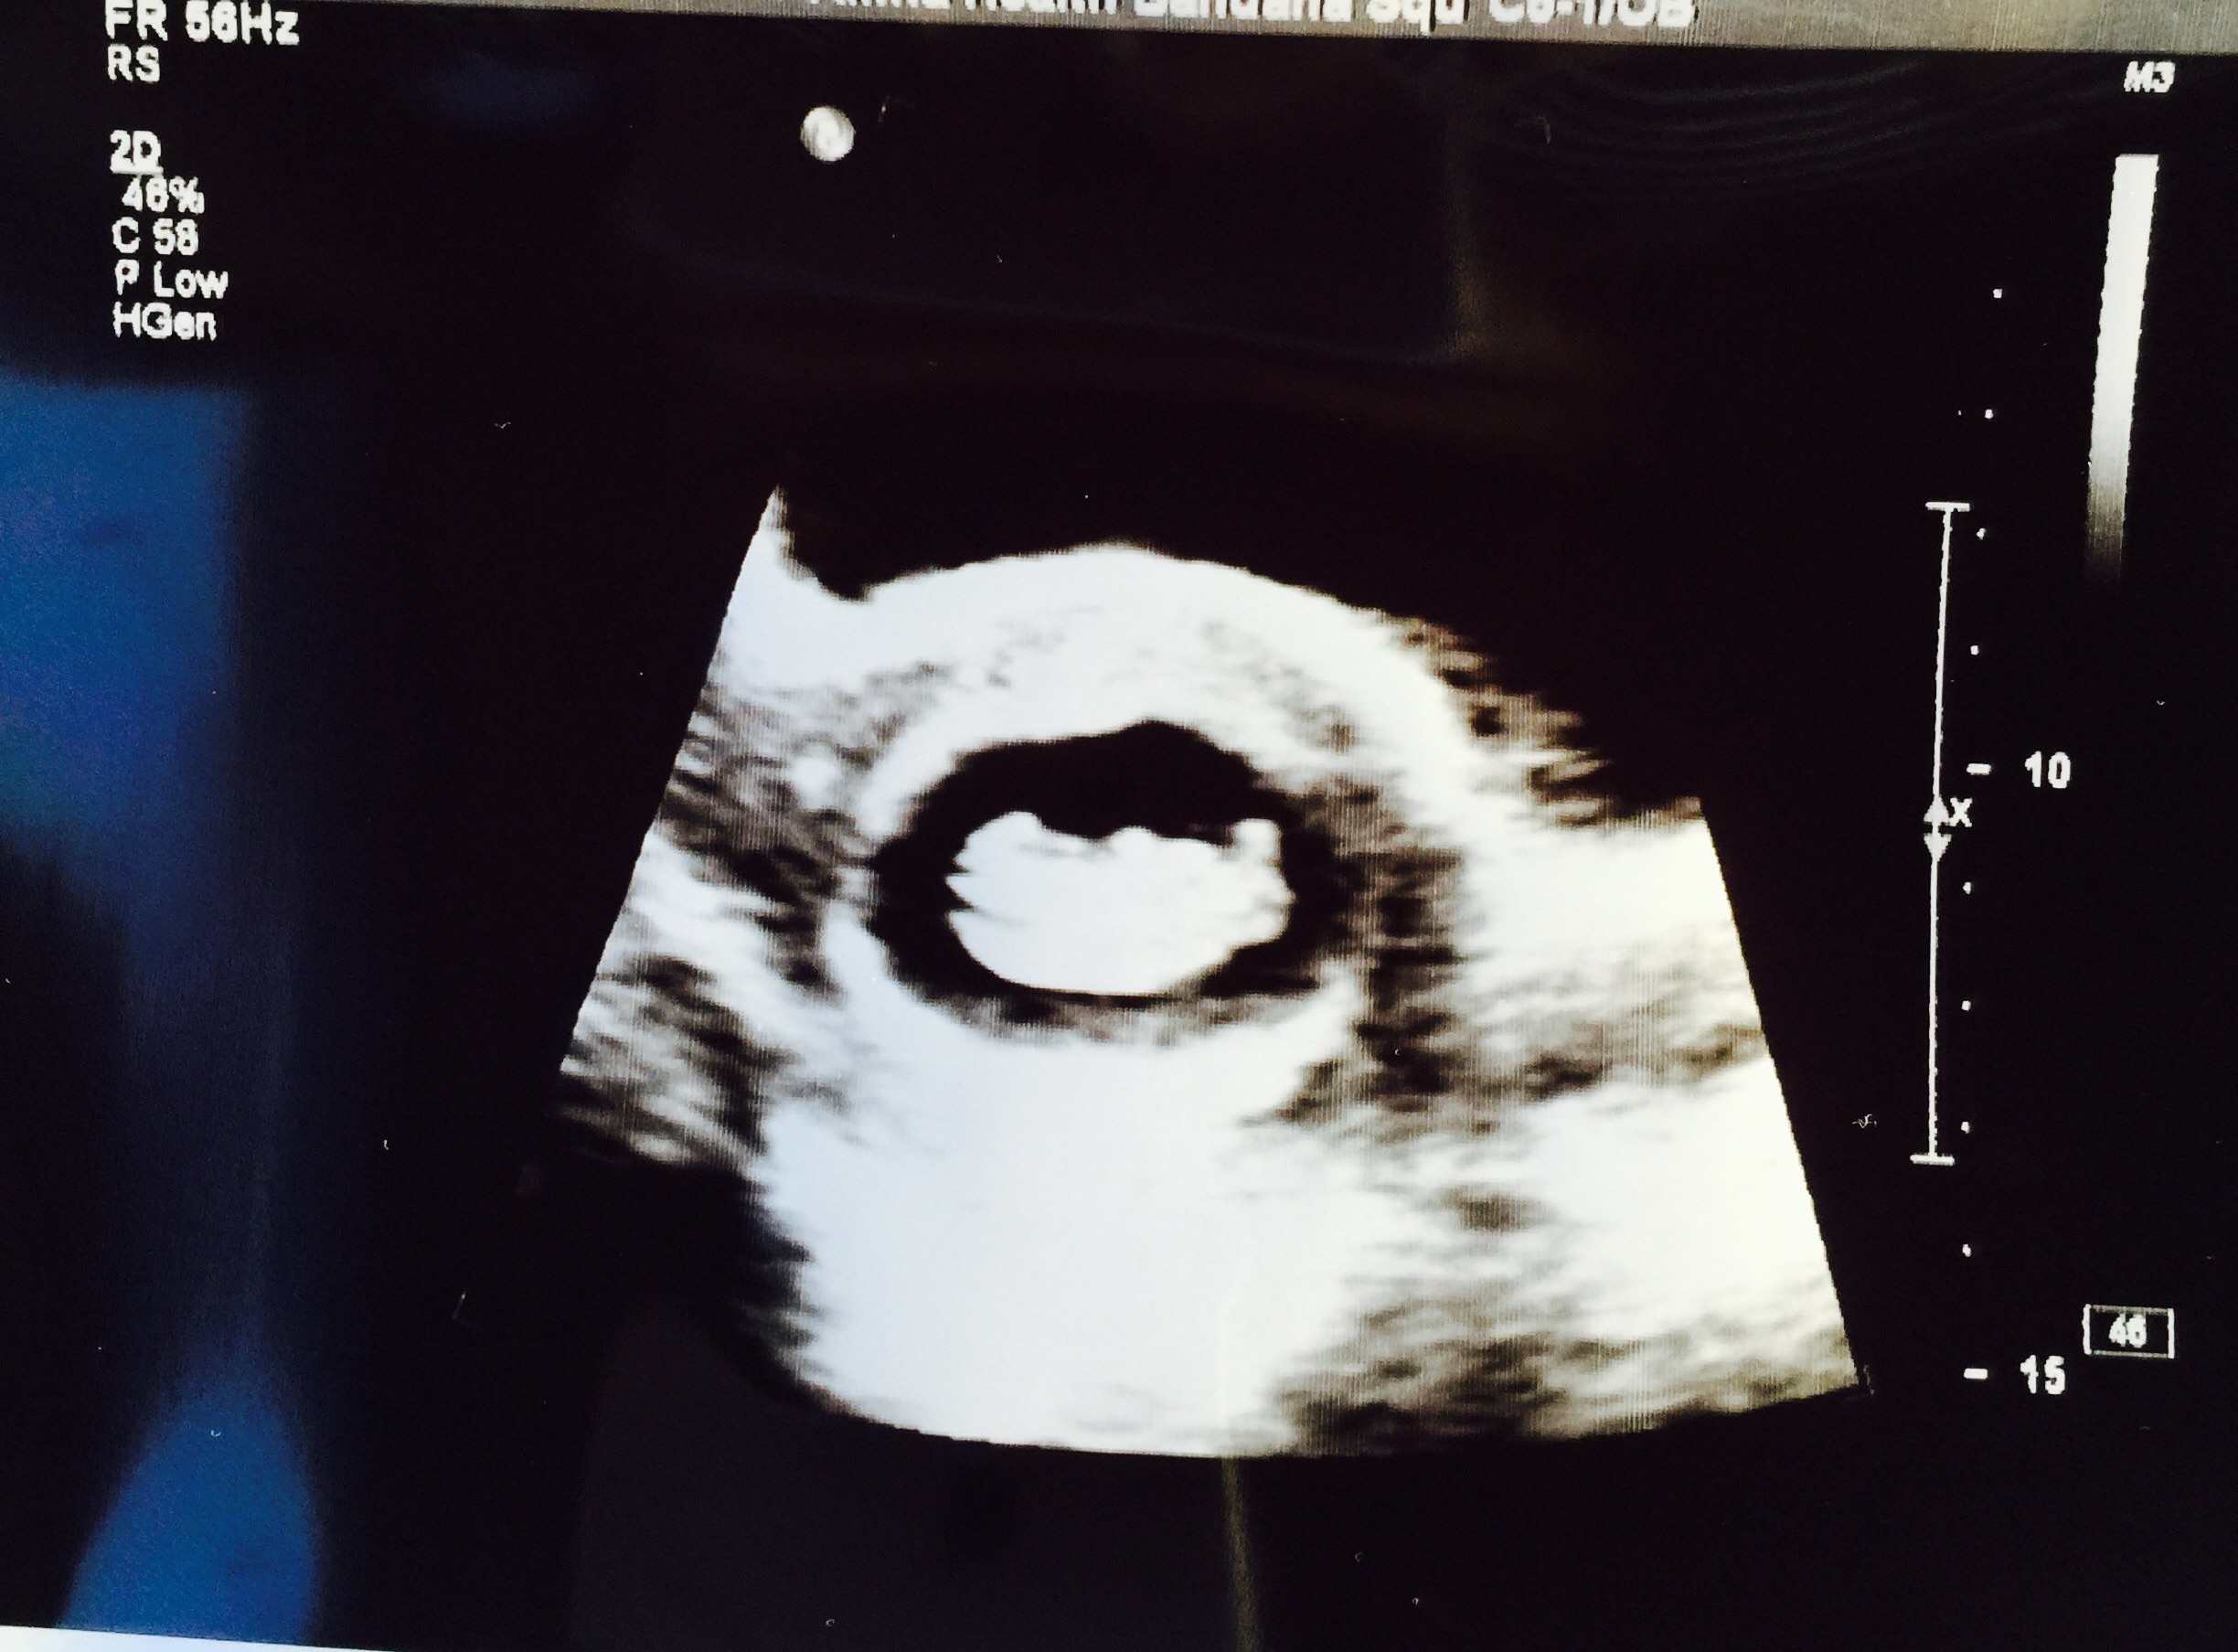

Here we are!!! I've been so excited to post this. My rainbow baby at 8w2d. Measured exactly as we thought with 165bpm. Baby looks a bit like a Lego character so I'm picturing "everything is awesome" playing on repeat as baby grows!!! Due April 13!